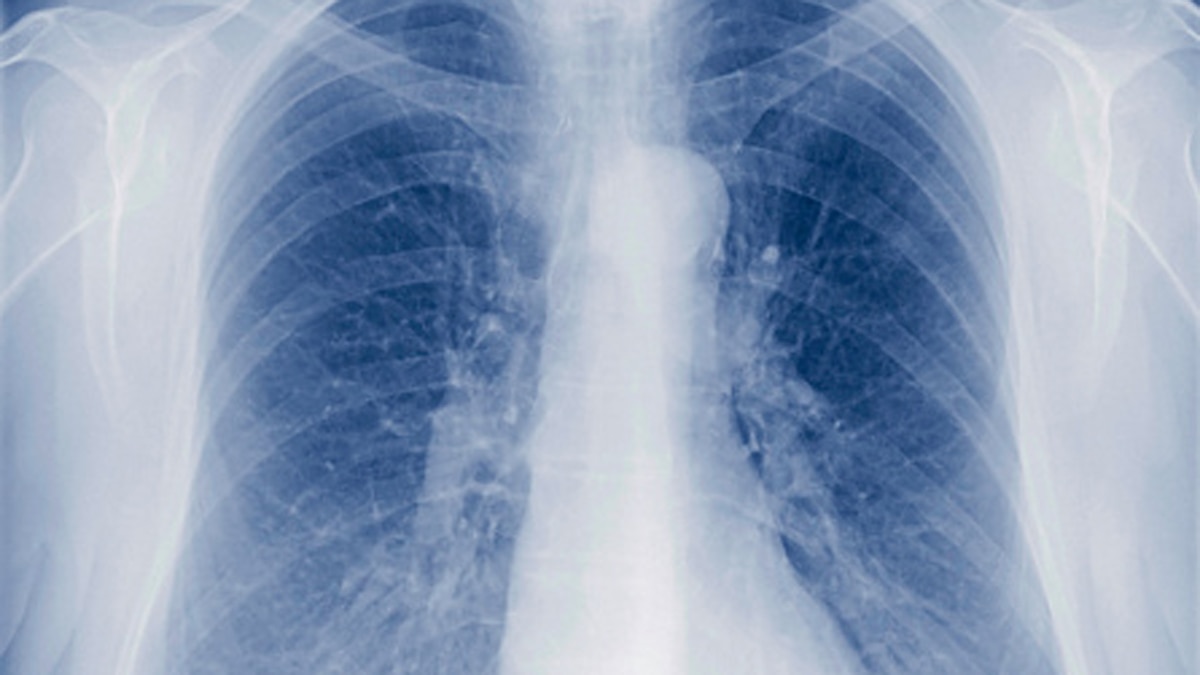

ट्यूबरक्लोसिस एक संक्रामक बीमारी है जो आमतौर पर फेफड़ों पर हमला करती है. धीरे-धीरे ये दिमाग या रीढ़ समेत शरीर के अन्य हिस्सों में भी फैल सकती है. टीबी के ज्यादातर मामले एंटीबायोटिक दवाओं से ठीक हो जाते हैं लेकिन इसमें बहुत वक्त लग जाता है. आमतौर पर इसकी दवा 6 से 9 महीने तक चलती है.

टीबी के लक्षण- लेटेंट टीबी के कोई लक्षण नहीं होते हैं. स्किन या ब्लड टेस्ट के जरिए इसे पता लगाता या सकता है. वहीं एक्टिव टीबी में 3 हफ्ते से ज्यादा तक कफ बना रह सकता है. छाती में दर्द, खांसी में खून आना, थकान, रात में पसीना आना, ठंड लगना, बुखार, भूख ना लगना और वजन कम हो जाना इसके मुख्य लक्षण हैं. अगर आपको इनमें से कोई लक्षण महसूस हो रहे हैं तो डॉक्टर से संपर्क कर अपना टेस्ट कराएं.